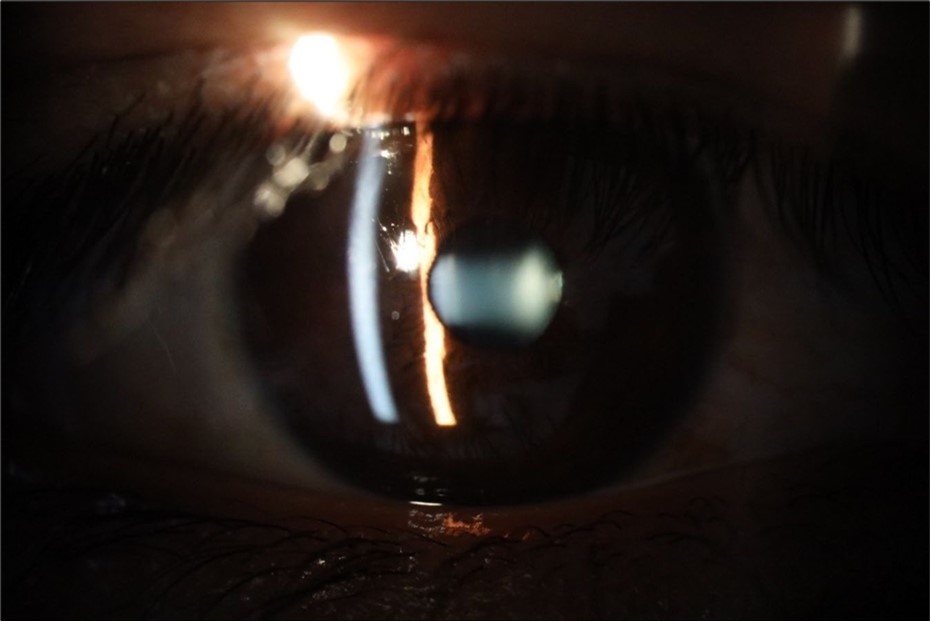

Figure 20.The mirror reflection of the affected (right) eye continues to improve.

Figure 25.Mirror reflection of the affected eye (right side), with good appearance. This indicates that the transparent media of the eyeball (Cornea, anterior chamber, lens, and vitreous) are in good condition.

Figure 26.The macrograph of the anterior segment of the right eye (affected) shows very good transparency of the cornea, anterior chamber, lens, and vitreous.